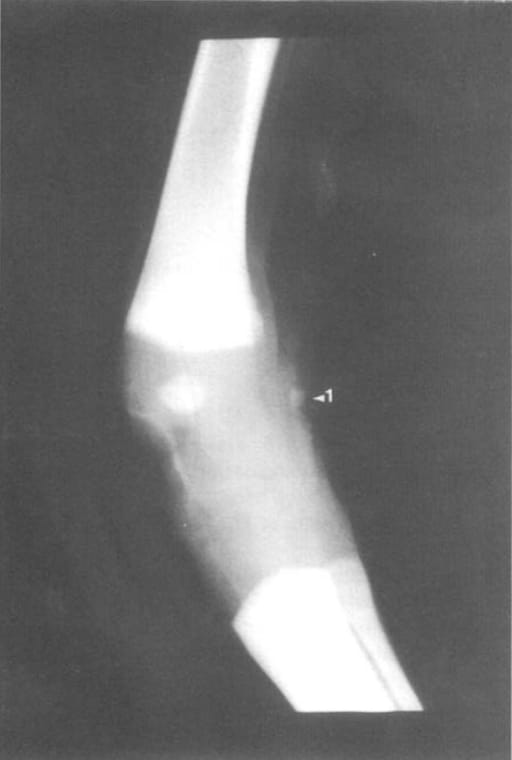

ML radiographic projection ofthe right carpus: Equine fetus of254 days. (1) Appearance of site of ossification ofthe Accessory carpalbone

The first carpal bone to ossify was the accessory carpal bone at approximately 254 days. This was followed by the radial carpal (274 days), intermediate carpal (278 days), and ulnar carpal bones (310 days). Ossification of third, fourth, and second carpal bones was hypothesized to occur between 285 and 295 days. For the tarsus, the calcaneus ossified first at about 125 days, followed by the astragalus at 220 days, with a secondary center appearing around 260 days. Central, third, fourth, first, and second tarsal bones ossified between 280 and 330 days. Ossification patterns were consistent across fetuses, though minor individual variability in size and presence of centers was noted.